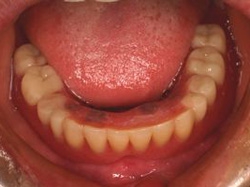

術後(鏡像)

術後口腔内(正面観)もう入れ歯は要らなくなりました。